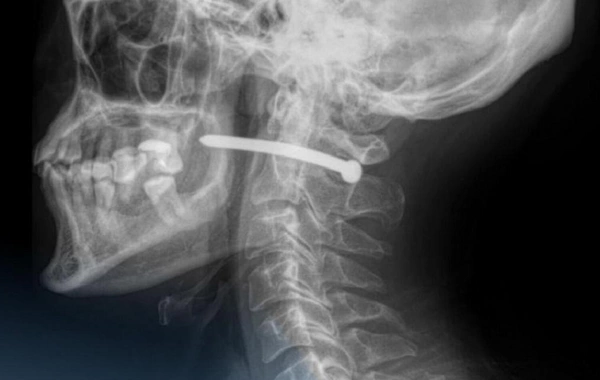

В Казахстане мужчина выстрелил себе в голову гвоздем и выжил

В Казахстане мужчина чудом выжил после того, как во время ремонта случайно выстрелил себе в голову гвоздем, сообщает портал Nur.kz. Инцидент произошел в Петропа...